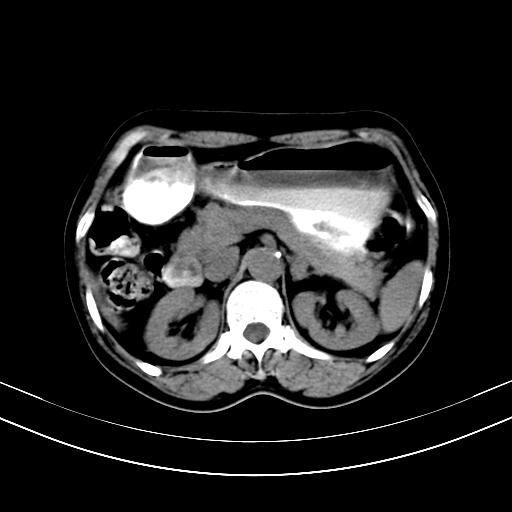

标题: CT12767:肝脏病变请会诊

补充强化片

胃内见充盈缺损,建议行胃镜病理检查,如果胃内无占位,则肝内考虑左叶、尾叶为包膜型肝癌,如有则考虑为转移瘤

胃内见充盈缺损,建议行胃镜病理检查,如果胃内无占位,则肝内考虑左叶、尾叶为包膜型肝癌,如有则考虑为转移瘤,左侧肾上腺 明显增大,成结节改变,本人考虑转移瘤可能性大。

胃内的充盈缺损因胃壁不厚,我个人考虑为胃内残留物。肝左叶及尾叶病灶,我首先考虑血管瘤,其次为肝癌。(尾叶的更低密度区太规整)

肝脏左叶和尾叶均见略低密度影,尾叶病变内见坏死?其边界清晰,形态规整1血管瘤,2肝癌待排

胆囊内见一略高密度影,息肉?

肾脏前方的是什么,肾上腺吗,

肝脏左叶和尾叶均见略低密度影,尾叶病变内见坏死?其边界清晰,形态规整1血管瘤,2肝癌待排3建议增强。

胃内充盈缺损考虑为胃内存留物,肝左叶和尾状叶两个病灶,均为低密度,建议增强。

考虑:胃体小弯侧胃癌(或平滑肌瘤恶化或平滑肌肉瘤)伴肝转移,左侧肾上腺转移不除外.

胃内充盈缺损考虑为肿瘤,肝尾叶及左叶肿块考虑转移瘤

胃癌肝内转移及肾上腺转移。

胃窦部占位伴肝及左肾上腺转移可能大,建议增强扫描。

肝脏左叶和尾叶均见略低密度影,尾叶病变内见坏死?其边界清晰,形态规整1血管瘤,2肝癌待排3建议增强或结合临床及超声与实验室检查

肝左叶及尾叶低密度灶,增强有渐进性明显强化,考虑血管瘤。胃内“充缺”首先要排除异物(食物),变换体位可鉴别。增强时机抓的不好,还应该有延时像。

谢谢楼主的增强片子,平扫没发现左侧肾上腺的问题很不好意思,可惜片子只有门脉期,所以还只有猜,肝脏的病灶在门脉期部分强化,首先考虑为血管瘤(其他的用一种病不好解释)胃要喝水就好了现在不好说是否有问题,左肾上腺的问题考虑是肿瘤。

做了增强后,可以明确胃是没有肿瘤的,肾上腺也没有肿瘤.肝左叶的病灶首先考虑血管瘤,应该再延迟,肝尾状叶的病灶仍不能排除肝癌的可能性.